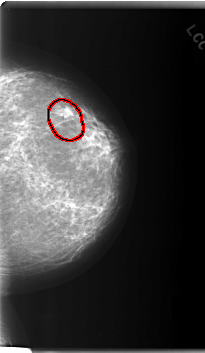

C_0165_1.RIGHT_MLO

FILE: C_0165_1.LEFT_MLO.OVERLAY

TOTAL_ABNORMALITIES 1

ABNORMALITY 1

LESION_TYPE MASS SHAPE ROUND MARGINS SPICULATED

ASSESSMENT 5

SUBTLETY 5

PATHOLOGY MALIGNANT

TOTAL_OUTLINES 1

BOUNDARY